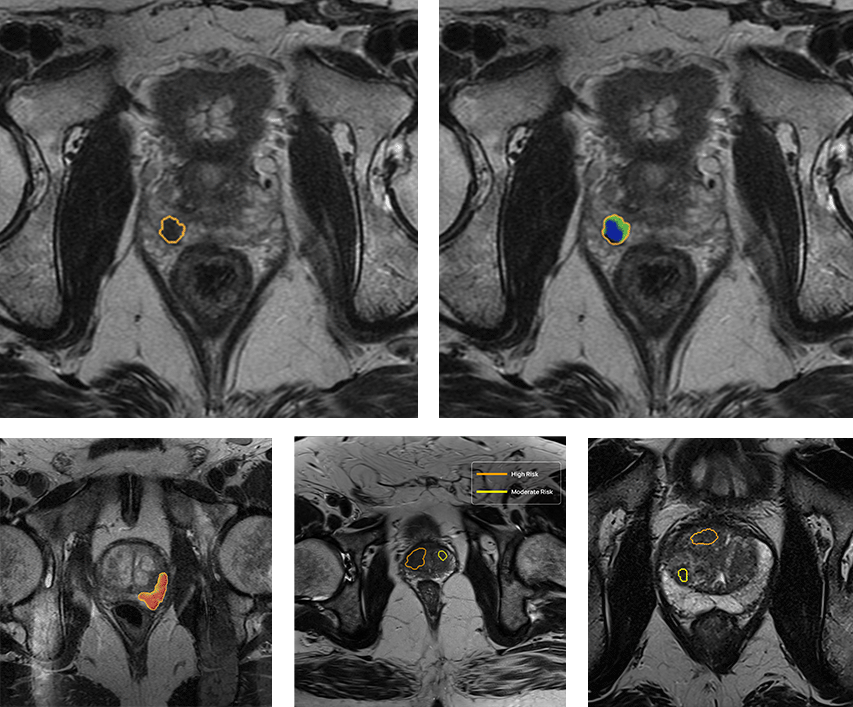

QP-Prostate is setting a new standard for accuracy, speed, and diagnostic precision. Its AI algorithm identifies and stratifies by likelihood intermediate and high-grade aggressive prostate cancer lesions, and provides a segmentation of the prostate. This allows Health Care Professionals to improve their diagnostic accuracy and fusion biopsy planning.

QP-Prostate automatically identifies and highlights prostate regions suspicious for aggressive prostate cancer, assigning each a confidence-based classification score.